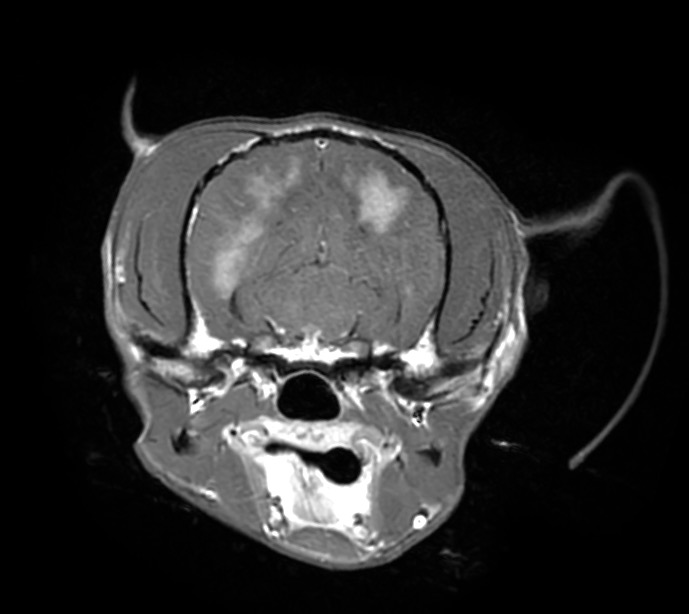

肉芽腫性髄膜脳脊髄炎と診断した犬の1例(MRI、GME、脳炎、神経症状、ふらつく、眼振)

頭部MRI検査では重度の脳圧亢進所見(脳の浮腫)、大脳の後頭葉領域に炎症所見が認められ、脳炎(特に肉芽腫性髄膜脳脊髄炎:GME)が第一に疑われるという結果でしたが、

脳圧亢進所見が重度のため脳脊髄液(CSF)検査が実施できず、確定診断には至りませんでした。